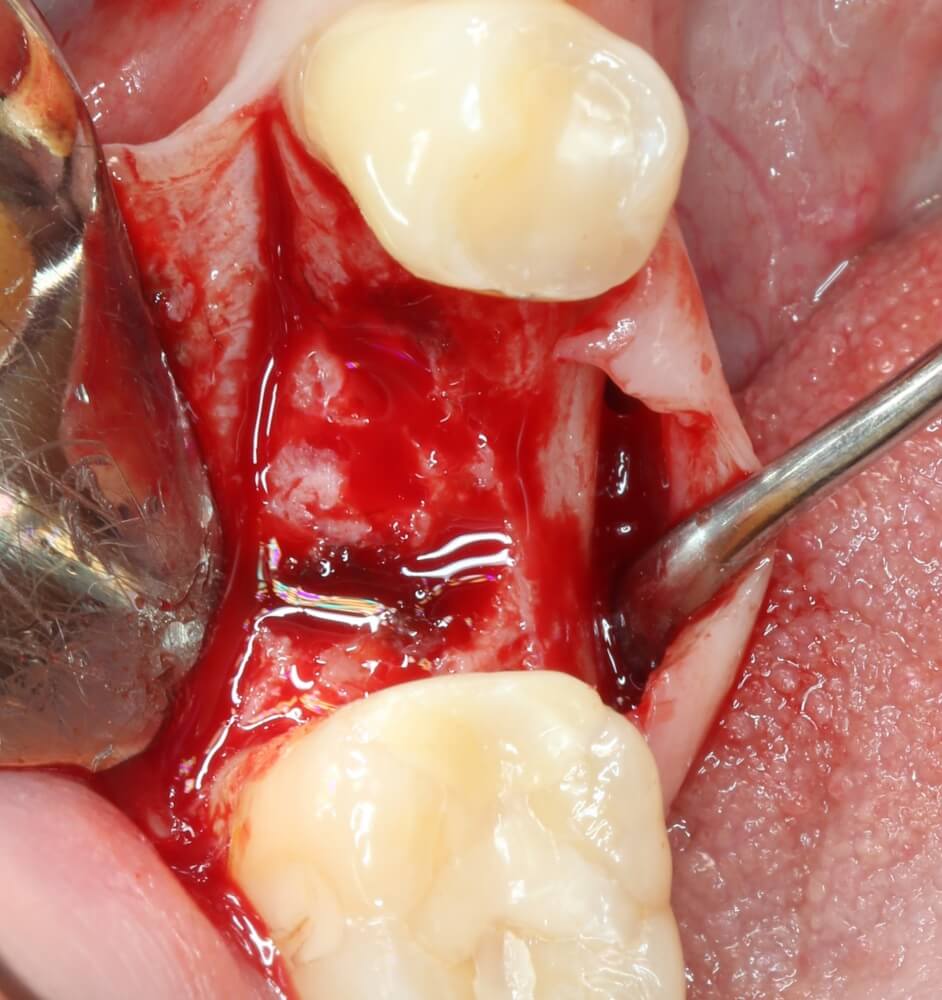

Рекомендации по установке имплантов. Для всех. Часть V.